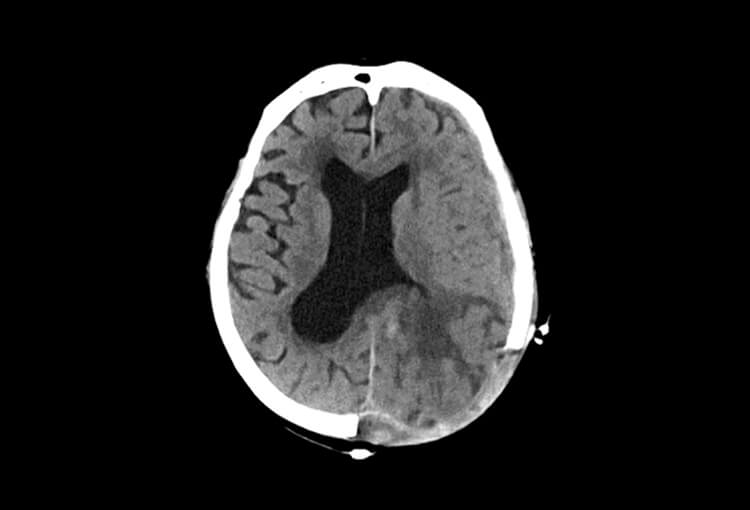

Before and After Denoising

120 kV / 20 mAs / 1 mm

Before FBP (Noise 189) VS After ClariCT.AI (Noise 46) 76% Denoising